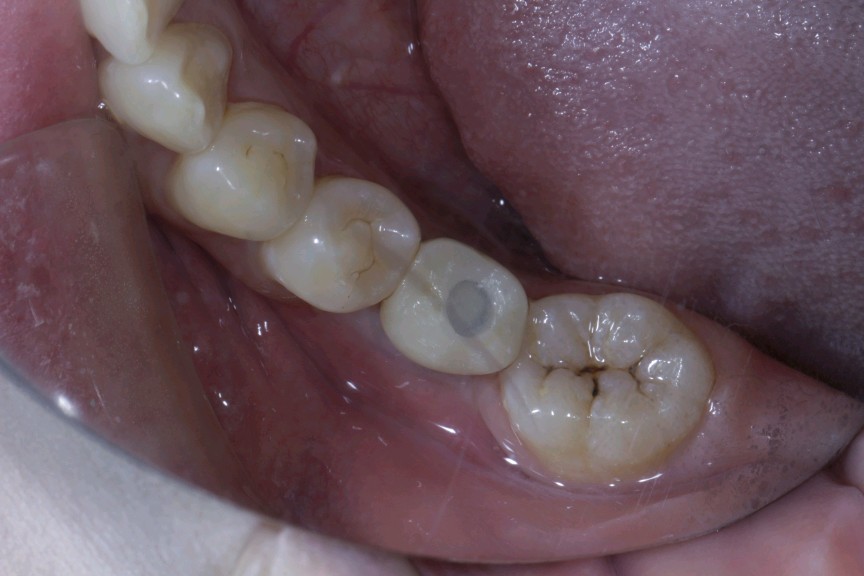

患者女,二十七岁,46牙体缺失近一年,牙槽崎吸收较多,粘膜无红肿、对合牙轻度伸长,邻牙轻微松动,龈周﹣。 x 示牙槽骨密度正常。告知患者治疗方案,患者选择种植修复。抽静脉血20ml,制作 CGF ,植Nobel Pcc 种植体4.3*10mm,上覆盖帽,颊侧骨缺损区植入 bio - oss 骨粉0.25g及 CGF ,盖 bio - Gide 膜及 CGF 膜,严密缝合。直至今日戴牙,咬合适宜,患者满意。